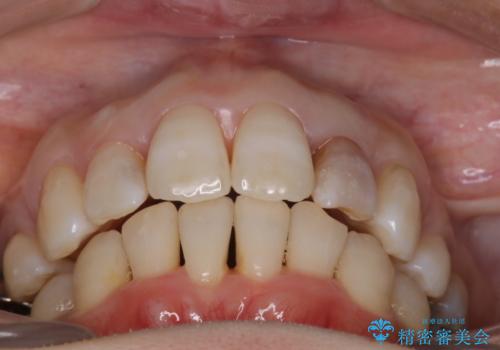

重度のガタガタと出っ歯をワイヤーによる抜歯矯正で整った歯並びへ

上顎の前歯は前方に傾斜して、下顎の前歯は強いガタガタが見られました。

前から4番目の歯を上下左右合計2本抜歯して、歯並びを整える計画としました。

ワイヤー矯正にて治療しました。